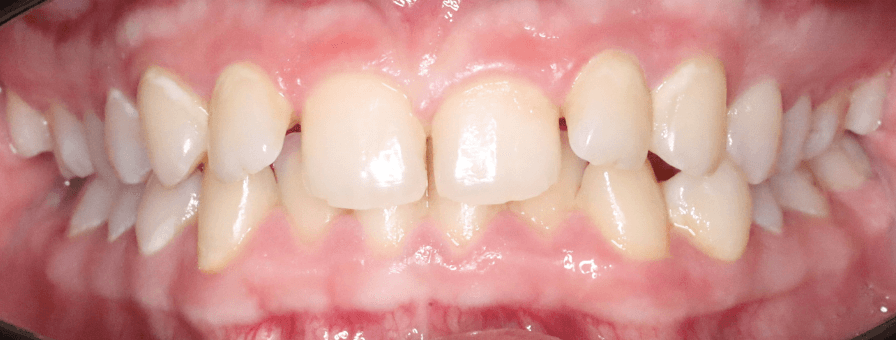

Corectarea Supraacoperirilor și Înghesuirilor Dentare

Pentru acest pacient de 20 de ani am rezolvat problemele complexe de înghesuire și supraacoperire folosind aparat fix bimaxilar. Evaluăm fiecare caz individual pentru a alege cea mai eficientă metodă de tratament. Rezultatele au fost obținute în aproximativ 1 an.